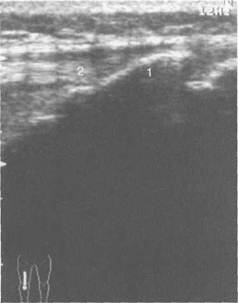

Рис. 19.123. УЗИ коленного сустава. 16 лет. Продольное сканирование.

1 — неполностью оссифицированная бугристость большеберцовой кости; 2 — собственная связка над­коленника.